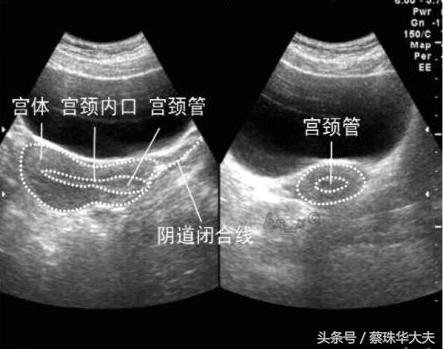

如果小胚胎长错了位置,长到输卵管内,那小神探也不怕,神探位置稍微变动一下,转到侧穹窿,一会儿就找到卵巢和旁边的输卵管。

而腹部探头(神探妈妈)虽然有时候比小神探厉害,但神探妈妈眼睛看表面东西厉害,找深部东西没有小神探那么灵活。

神探妈 妈看子宫和卵巢输卵管只有通过肚皮皮肤,肚皮下脂肪,才能照到达子宫表面,而且有时候爱捣乱的肠子还会来砸场。

所以神探妈妈只能找来帮手,让膀胱充满尿才能推开爱捣乱的肠子。但这个膀胱助手也不是个省游的灯,膀胱里的尿太少,神探妈妈嫌弃这个助手不得力,尿太多,主人受不了。只能凑活着看吧。